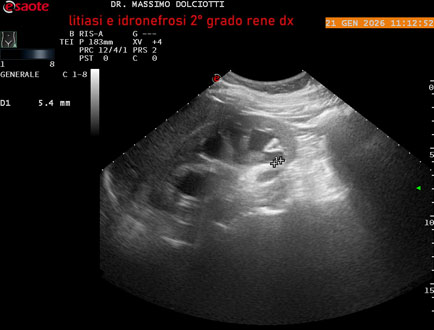

Data inserimento: 22/01/2026

Ecografia del: 21/01/2025

Strumento: Esaote MyLab Eight

Sonda: Convex Multifrequenza 1-8 MHz

Età Paziente: M 27 anni

Motivazione dell'esame: dolore al fianco destro da 3 mesi.

Commento all'esame: le immagini ed il video documentano il rene destro in sede, con ecostruttura disomogenea per evidenza, alla pelvi renale, di immagine iperecogena delle dimensioni di 16,2 mm, con cono d'ombra posteriore, da ricondurre a litiasi ed una formazione simile, di minore entità, al polo inferiore, delle dimensioni di 6,8 mm. Rene dx con diametro longitudinale di 122 mm (v.n. 90-120 mm) x 63 mm e parenchima renale dello spessore di 15 mm (v.n. > 13 mm). Rene dx con idronefrosi di 2° grado.

Conclusioni: litiasi e idronefrosi di 2° grado al rene destro (lithiasis and second-degree hydronephrosis of the right kidney).